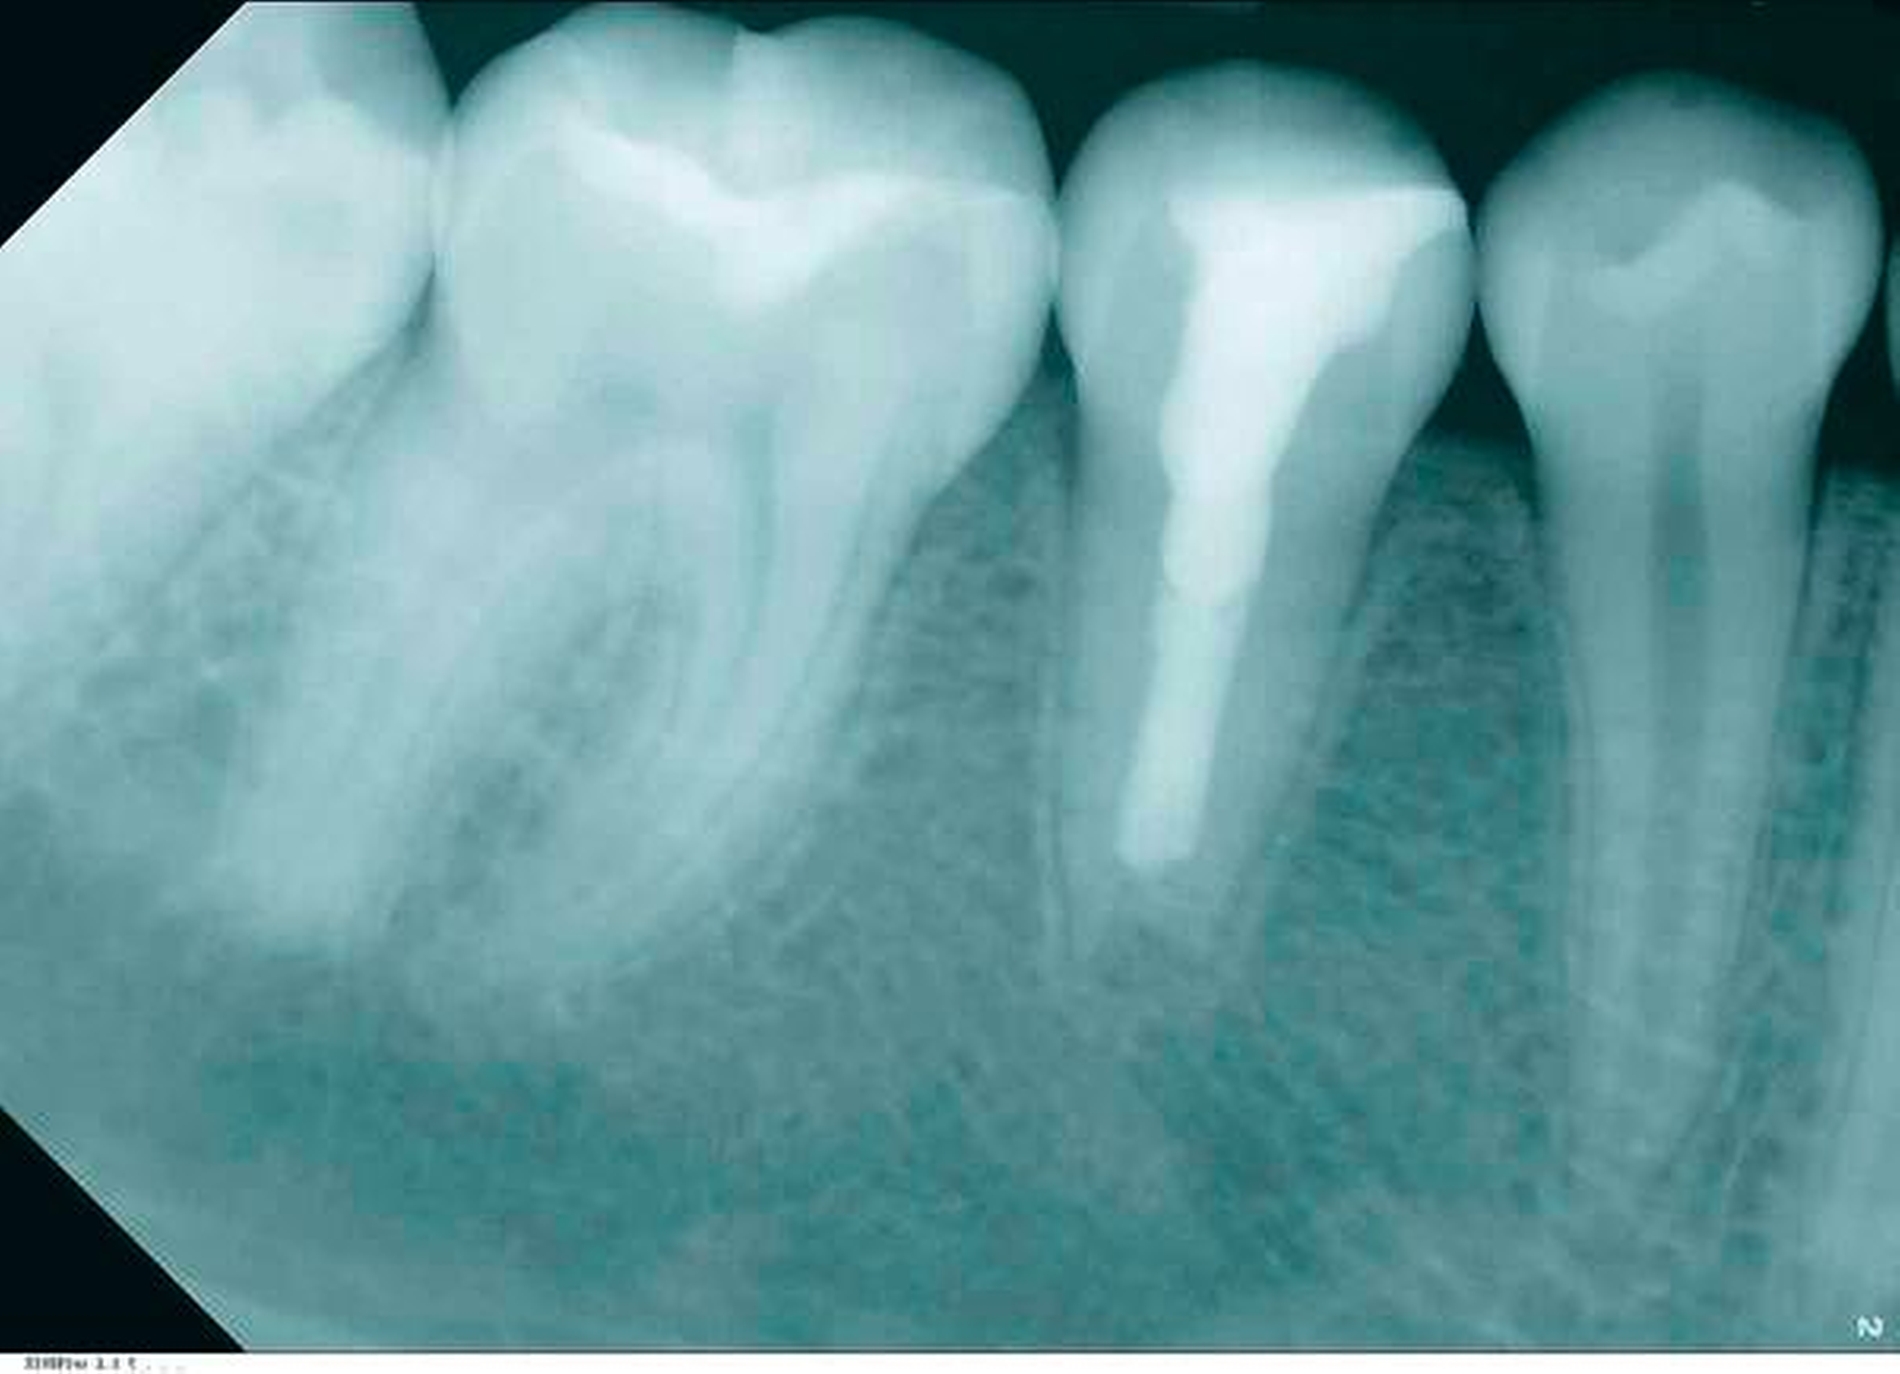

Die Patientin klagte weder über eine Symptomatik, noch zeigten sich Entzündungszeichen im Verlauf. Die sporadischen Schmerzen und das Druckgefühl im Kiefer waren beim ersten Kontrolltermin nach vier Wochen gänzlich abgeklungen. Der Klopfschall war unauffällig, der Zahn reagierte nicht auf Perkussion und das Vestibulum war schmerzfrei bei Palpation. Nach vier Monaten erfolgte ein Verlaufsröntgenbild (Abbildung 11), bei dem bereits eine Hartsubstanzausbildung und ein fast vollständiger Rückgang der Läsion zu erkennen sind. Nach zehn Monaten wurde ein weiteres Verlaufsröntgenbild angefertigt (Abbildung 12). Die Läsion scheint vollständig rückläufig und mit Hartgewebe ersetzt zu sein. Die radiologische Nachkontrolle nach 18 Monaten zeigt eine deutliche Dickenzunahme des Dentins im Vergleich zur Ausgangssituation und stabile periapikale Verhätnisse (Abbildung 13). Der Zahn ist nach wie vor symptomfrei und in situ.